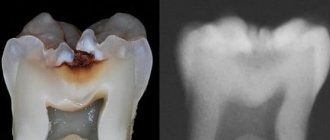

Caries is a common disease that damages the hard tissues of the tooth. At first, the disease is asymptomatic, so many patients do not attach much importance to the problem. Visiting a clinic for professional help is associated with the appearance of acute pain or transition to a chronic form, when discomfort is felt constantly.

At the same time, the patient is interested in the question: is it painful to treat caries ? The answer is clear: the discomfort from treatment is minimal, especially in comparison with the pain caused by a tooth damaged by cariogenic bacteria.